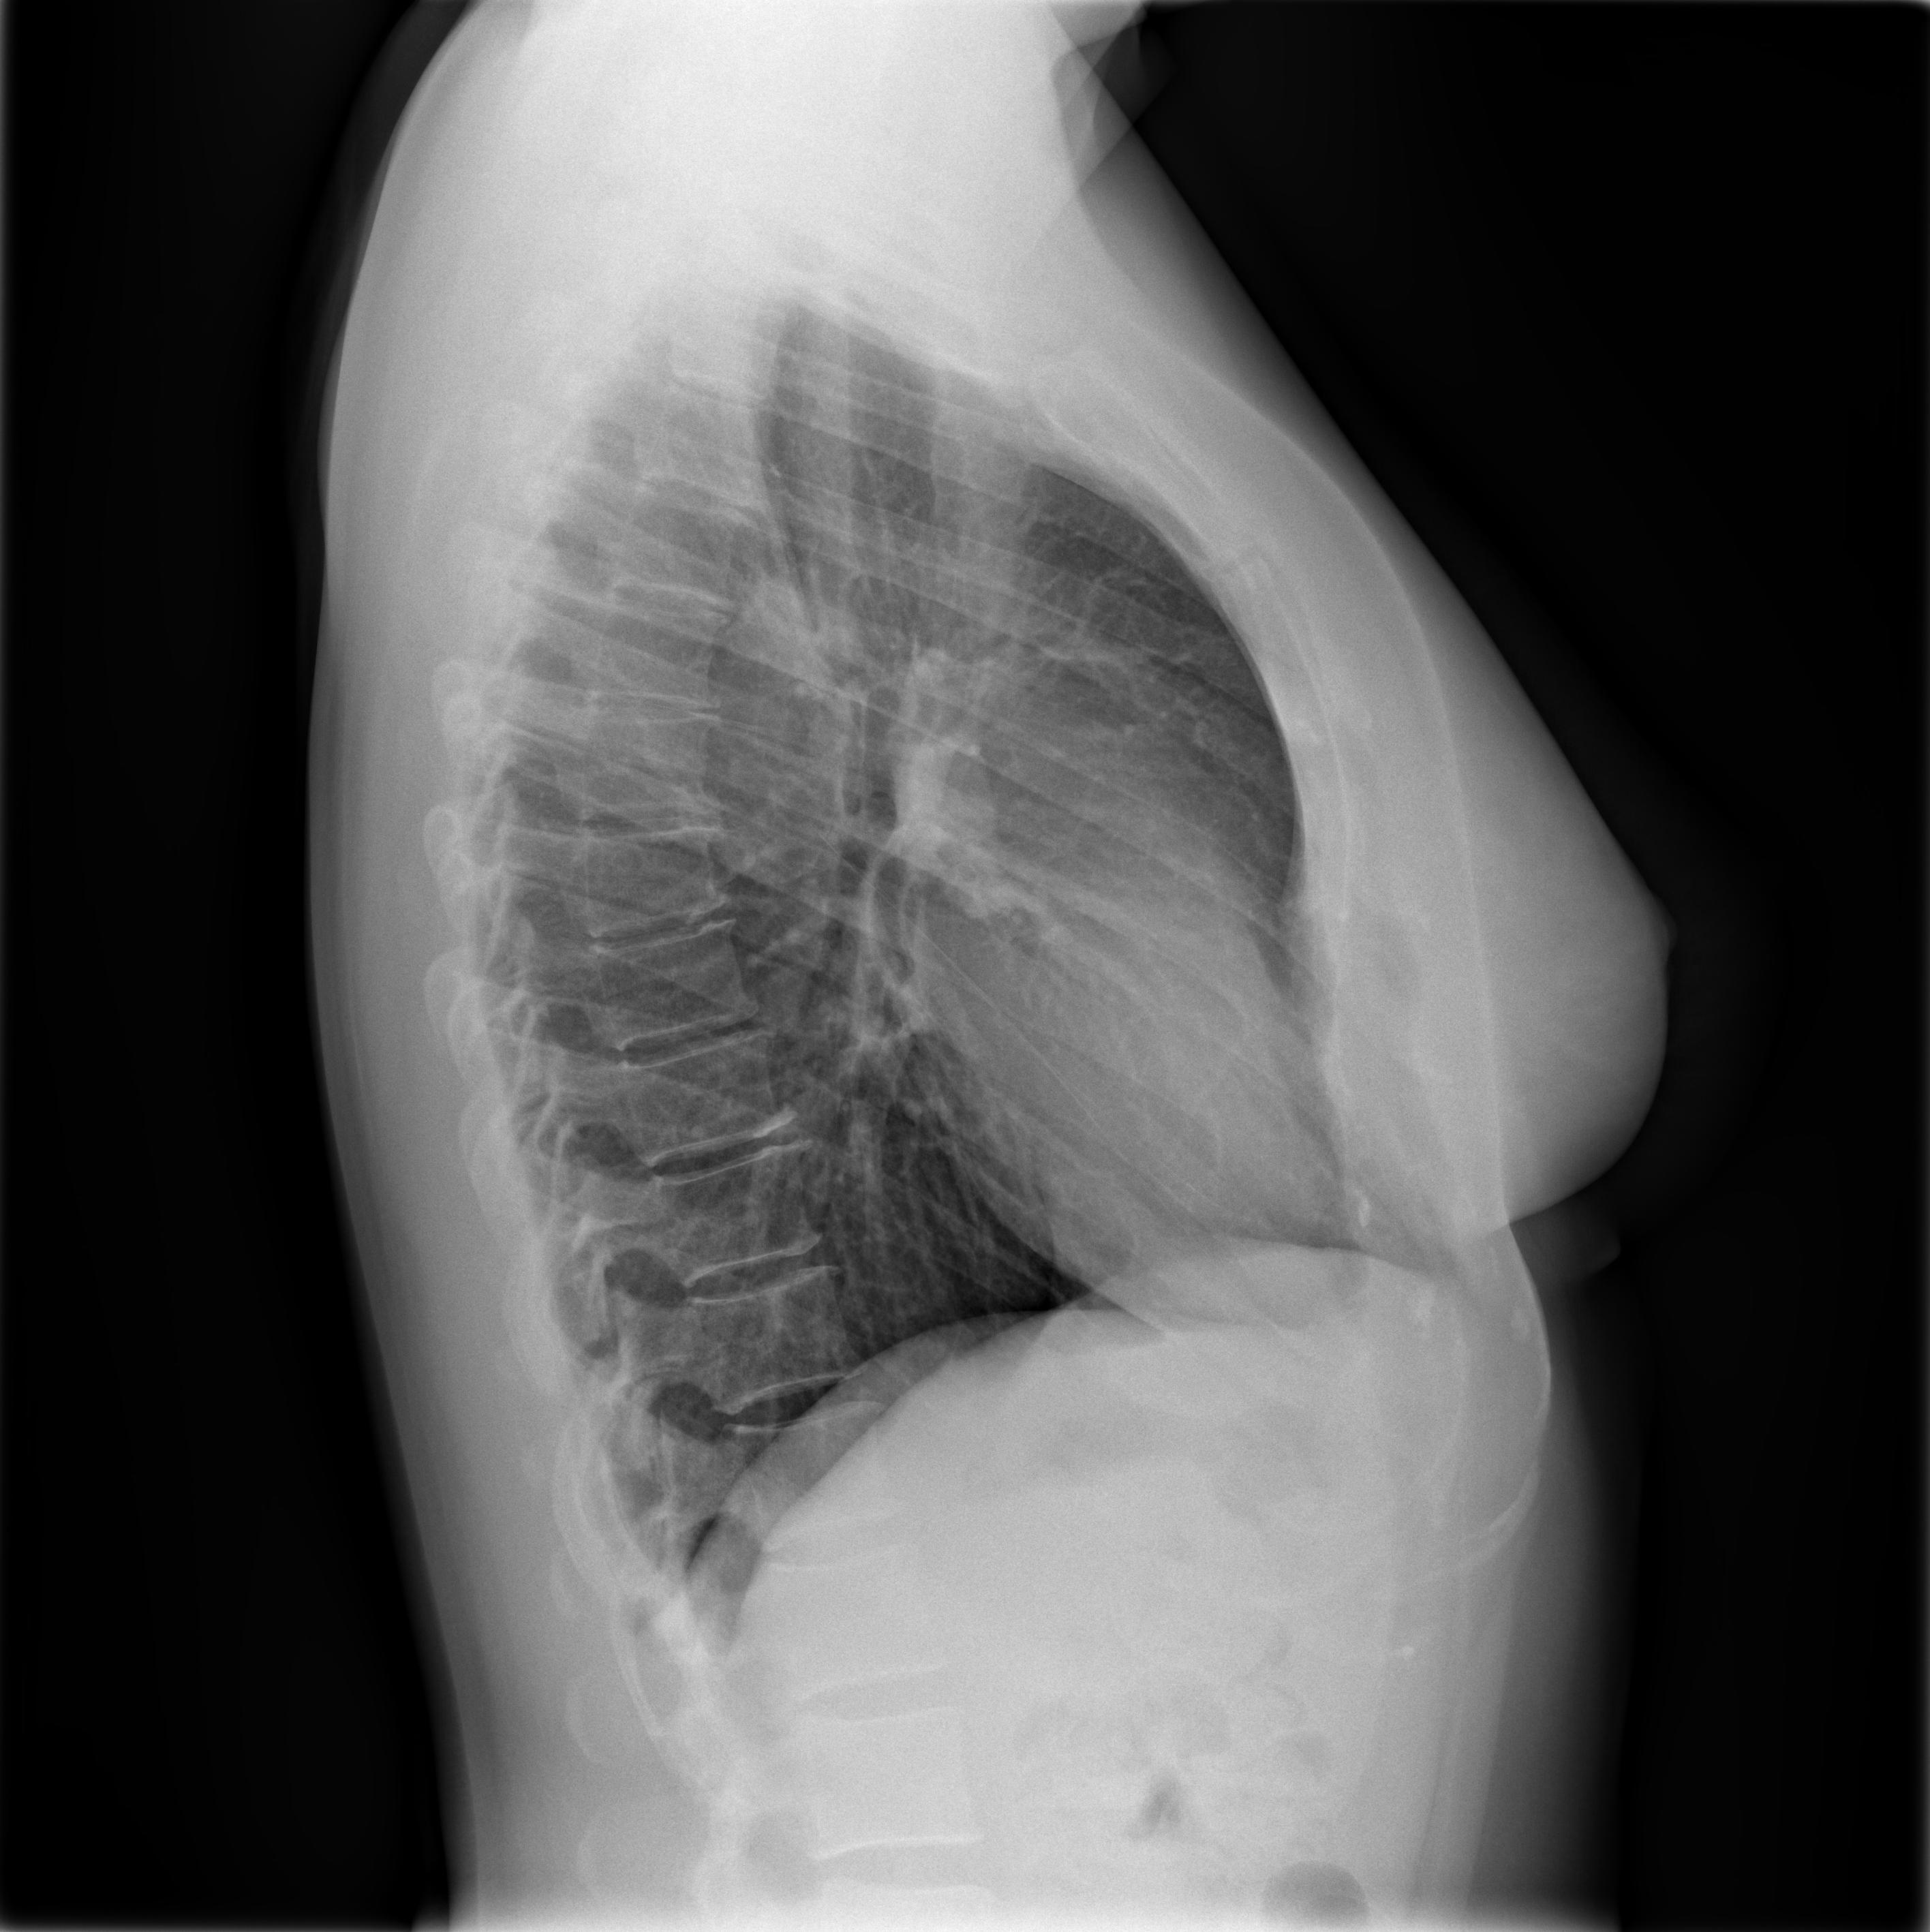

chest x-ray chest x-ray chest x-ray

chest x-ray

I had a short break of a few days, and the medical checkups resumed on October 27th, when a few things happened. The first of these things was a chest radiology exam, which showed that no pulmonary lesions were present or suspected. Another piece of the puzzle falling into place.

I included here the two x-ray images, along with a recap of the protocol they used for the exam. I will be honest, I don’t understand it (all), but I couldn’t help but thinking that this is data that plays a crucial role, too: a different protocol might have shown things differently? more of it, less of it?

Chemotherapy day (finally) arrived: the sooner I started, the better, obviously. Not sure what happened on the day, but I fainted while getting ready. The pain from the port surgery, the tiredness, the stress of it all, I just went down on my face. My oncologist suspected a pneumothorax (a collection of air outside the lung but within the pleural cavity) so I was sent to radiology for some x-rays.

They checked my lungs during inspiration (first image) and expiration (second image): you can clearly see Portia with the catheter getting into my subclavian vein.

Luckly enough, I didn’t have a pneumothorax, so we went ahead with chemotherapy.